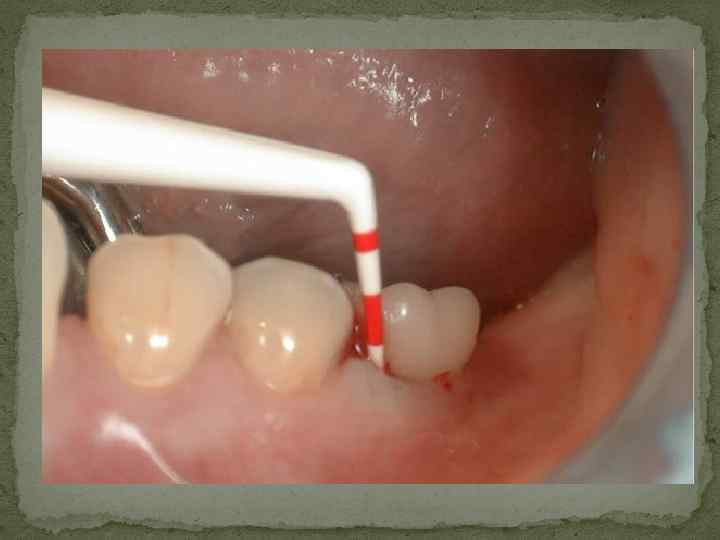

Клинические методы